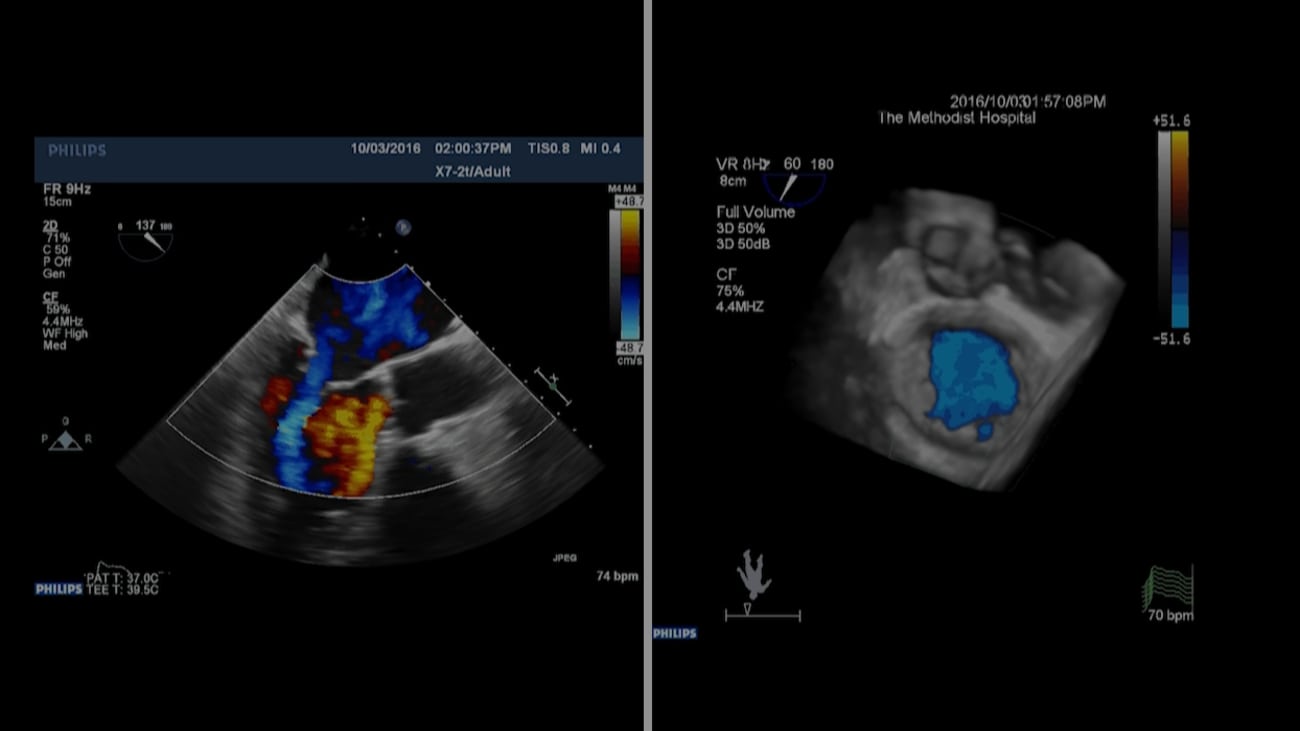

Mitral Valve Clip 92 Year Old Male (Dyspnea at Rest) Houston Valve Clinic Houston Methodist innovative valves create a legacy for the future. “the houston methodist debakey heart & vascular center’s valve clinic team has been at the very forefront of this pioneering innovation in minimally. heart valve disease specialists within the valve clinic at houston methodist debakey heart & vascular center are nationally. tavi and tavr procedures are only performed. Valve Clinic Houston Methodist.